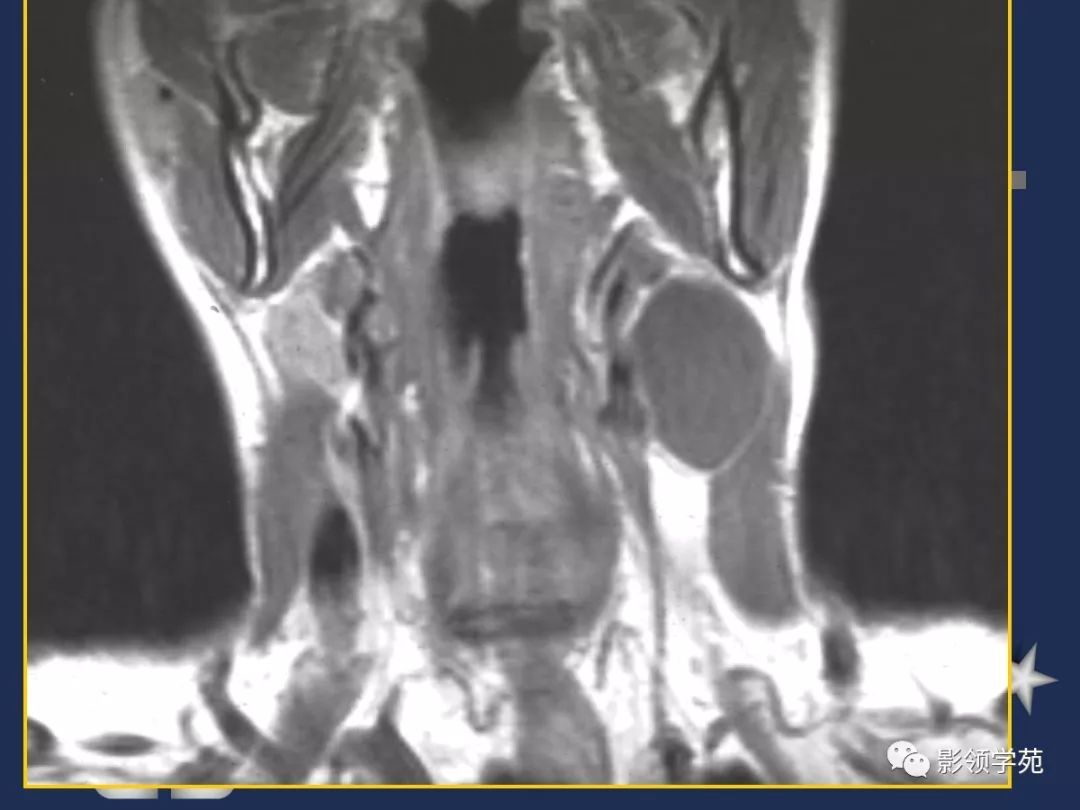

- 腮裂囊肿

- MRI上实性肿块在T1WI上呈等低信号,在T2WI上呈高信号,囊变区呈长T1长T2信号,钙化在T1WI及T2WI上均呈低信号。